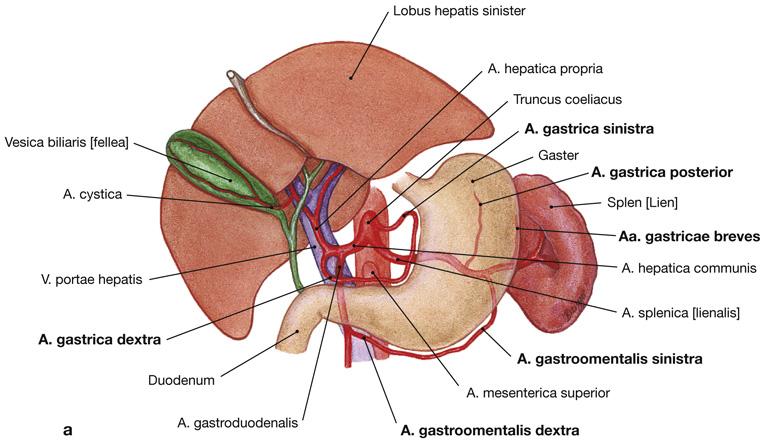

Fig 3.22: tr. coeliacus

diaphragma (groen) oesophagus -

ventriculus = maag

duodenum milt -

aorta abdominalis

|

|